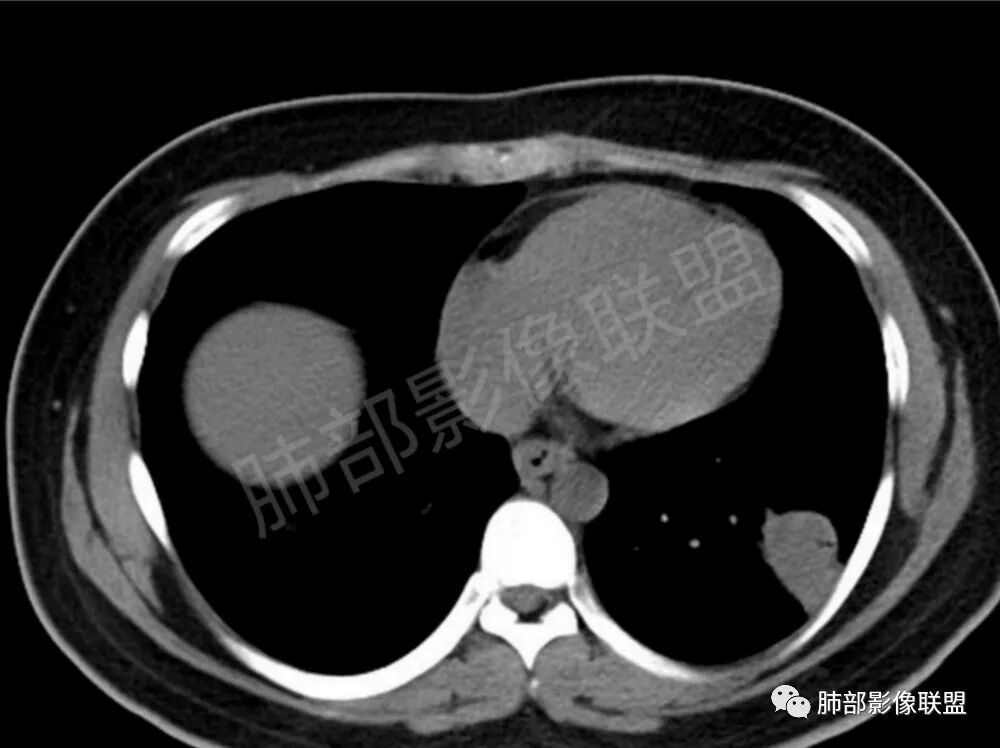

两肺多发结节性,大部分位于胸膜下,部分结节周围可见晕征。局部结节内可见扩张的支气管,纵隔淋巴结大,脾大,22岁男,HIV阳性,常规先考虑隐球菌。鉴别淋巴瘤,结核,马儿。

男,22,半年前咳嗽伴少痰,查HIV阳性,痰查TB阳性,既往有肺部斑片影伴空洞、纵隔淋巴结肿大、脾大。SCC、CA50、CA199、FER增高,此次胸部CT:两肺多发结节影,部分沿血管束分布,部分贴胸膜下,大小不一,密度不一,部分较散、边缘模糊,部分较实、圆钝、周围模糊晕,部分结节有支气管进入穿行自然,部分结节有血管分支自如通过。考虑HI∨相关淋巴增殖类病变,淋巴瘤?LYG?鉴别PC、TB。

青年男性,半年前咳嗽,HIV阳性,结核DNA阳性,肿标糖类抗原和铁蛋白增高。外院影像有纵隔淋巴结增大伴脾大,肺部病灶空洞。现在影像:肺内多发沿支气管分布(有支气管充气征,长轴沿支气管分布)及胸膜下分布(平行于胸膜)的大小不等结节,个别伴有空洞,双侧腋窝淋巴结肿大。纵隔图片不够,是否还有淋巴结肿大未知,脾脏未显示。

1、HIV相关淋巴瘤,有HIV阳性,有纵隔及腋窝淋巴结肿大,肺内病灶沿支气管分布(中轴淋巴间质)及胸膜下分布(周围淋巴间质),有脾大,这个是必须要考虑的。但是原来的影像是肺斑片影伴空洞,又有疑问,需要穿刺明确。

2、卡波西肉瘤,肺内多发结节,影像改变无明确火焰征,原来是斑片影伴空洞改变,不是太好解释。